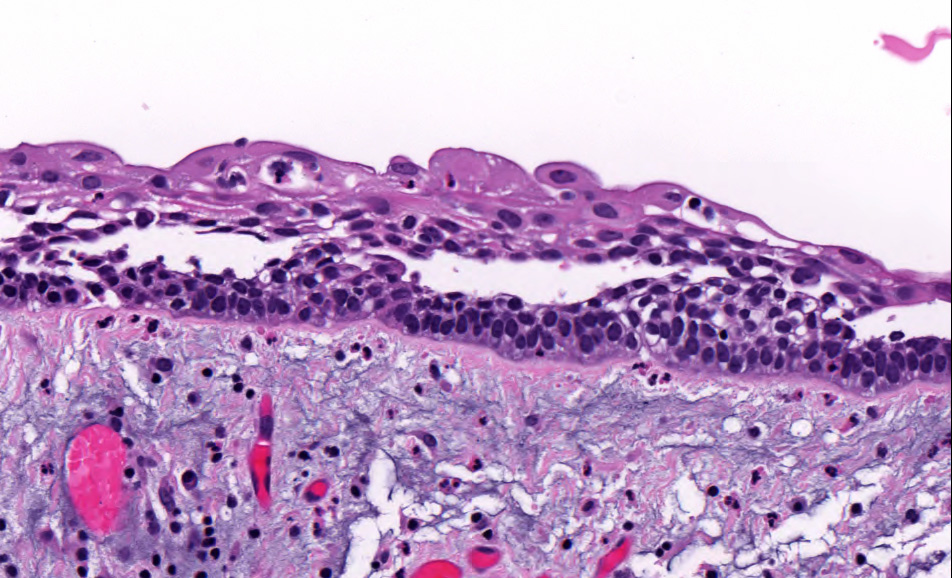

Microscopic (histologic) images

Contributed by Kelly Magliocca, D.D.S., M.P.H. and Anne C. McLean-Holden, D.M.D., M.S.

- Ameloblastoma, unicystic type has 3 histopathological patterns

- Single cystic lesion lined by ameloblastic epithelium that shows typical features of ameloblastoma in some areas, including columnar basal cells in palisading arrangement with vacuolated cytoplasm, hyperchromatic nuclei polarized away from basement membrane

- Suprabasal cells loosely textured and noncohesive resembling stellate reticulum, epithelial invagination, epithelial edema and separation

- Within the epithelial islands and cords of conventional ameloblastoma and the cystic epithelial lining of unicystic ameloblastoma, the odontogenic epithelium shows similar changes:

- Columnar cells with hyperchromatic nuclei at basal layer, exhibiting peripheral palisading

- Cells show reverse polarization away from basement membrane (Vickers-Gorlin change)

- Subnuclear vacuolization

- Suprabasal cells with a loose, network-like arrangement, recapitulating stellate reticulum formation seen in normal odontogenesis